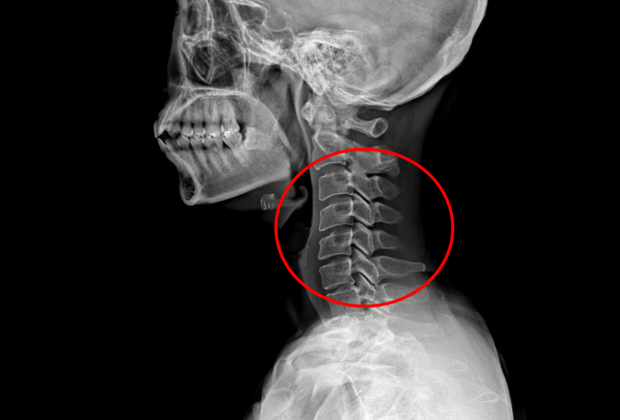

기사 이해를 돕기 위한 사진(기사 내용과 무관).클립아트코리아

목 디스크 수술 환자에 대한 사후 처치를 제대로 하지 않아 환자를 숨지게 한 혐의로 재판에 넘겨진 신경외과 전문의에게 벌금형이 선고됐다.

A씨는 지난 2021년 6월 21일 인천의 한 병원에서 환자 B씨(60)의 목 디스크 수술을 집도한 뒤,수술 부위에 발생한 혈종을 확인·제거하는 등 필요한 조치를 하지 않아 환자를 숨지게 한 혐의로 기소됐다.

목 디스크 수술은 수술 직후 혈압 상승이나 지혈 매듭 이탈 등으로 수술 부위에 혈종이 생길 가능성이 높은 것으로 알려져 있다.이에 수술 후 엑스레이(X-ray) 검사를 실시하고,혈종이 확인되면 제거해 기도 압박을 해소하는 등의 조치가 필요하다.

그러나 A씨는 수술 당일 회진을 마친 뒤 엑스레이 검사 결과를 확인하지 않은 채 오후 6시 3분께 퇴근한 것으로 조사됐다.간호사가 촬영한 엑스레이 영상에는 혈종과 출혈이 나타났지만,A씨는 이를 확인하지 않았고 이후에도 검사 결과를 요청하거나 확인하지 않은 것으로 드러났다.